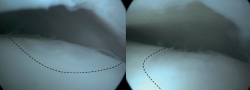

Retrograde drilling is a non-transarticular technique, using fluoroscopy for visualization of the talus, which allows for debridement and drilling of the subcartilaginous cyst. Retrograde drilling can be considered as a surgical intervention for cystic OLTs with an intact articulate cartilage layer(22). Retrograde drilling allows for the penetration of the necrotic sclerotic zone for bone marrow stimulation, without damaging the intact cartilage surface(37). Similar to BMS, retrograde drilling causes disruption of the intraosseous blood vessels and thereby promoting subarticular bone filling of the cyst. After exposing the talus using anteromedial and anterolateral portals, a Kirschner wire will be positioned under fluoroscopic control, transtalar from the opposite talar neck into the subchondral sclerotic zone(37).